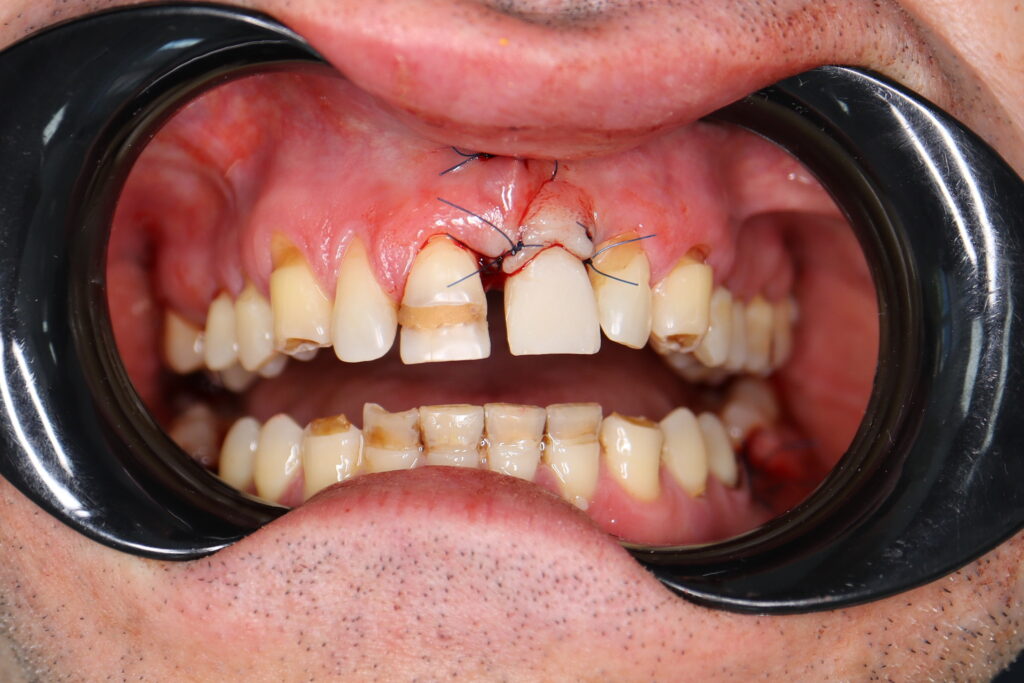

Ситуация до лечения

Пациент обратился с жалобами на эстетические недостатки.

Диагноз: Частичная адентия, клиновидные дефекты, гипоплазия эмали.

пациент до имплантации

Результаты хирургического этапа